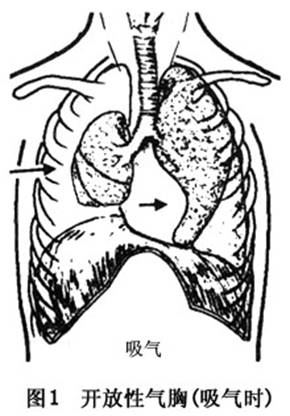

傷側肺可完全萎陷,縱隔推移至對側,壓迫健側肺,通氣不足,塌陷肺泡區域的血液不能氧合,肺動、靜脈分流增加,引起全身缺氧及二氧化碳蓄積。吸氣時傷側肺內部分殘氣吸入健側肺內,呼氣時健側肺部分殘氣進入患側肺內,稱爲縱隔撲動。加重缺氧及二氧化碳瀦留(圖1,2)。